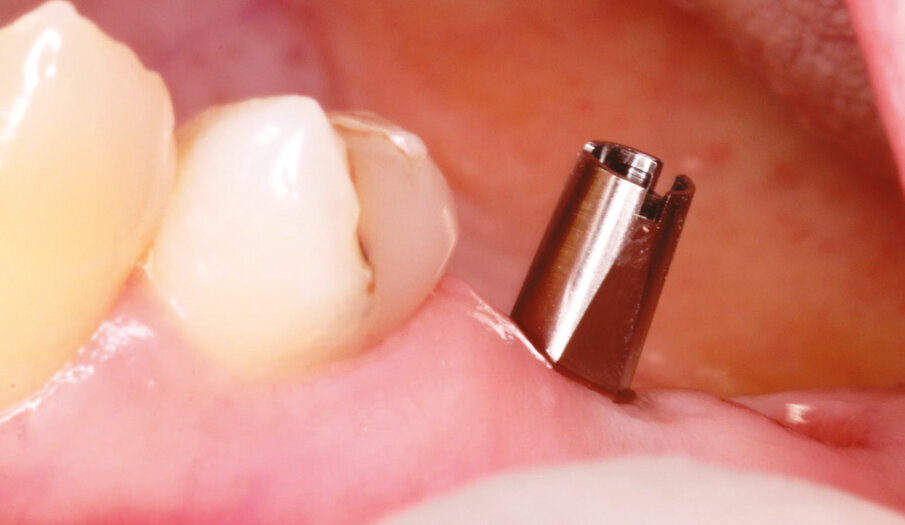

Fig.6: Implant placed flapless in #25.

Fig.7: Axiom concept for healing cap selection to form transmucosal passage for excellent final aesthetics.